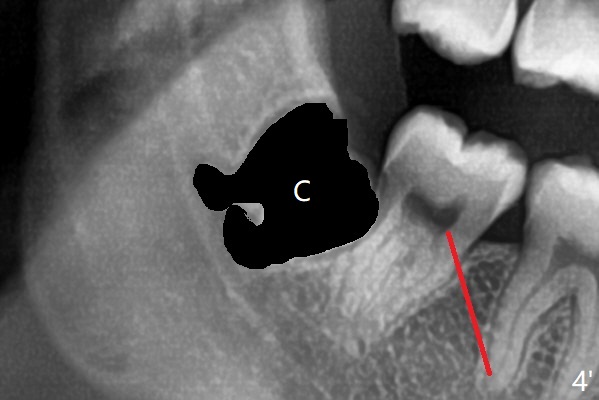

A 22-year-old man will return for 3rd molar extraction (4 of them, Fig.1-4). Prepare 2 or 3 #15 blades and 1-2 extra surgical burs. Since the third molars may overlap with the second ones, oblique incision (red line in Fig.4') will be mesial. Place Collagen and Osteogen plugs in the #32 and 17 sockets, respectively (Fig.4': C, O). As the roots are short and bone formation distal to the 2nd molars is critical, the plugs will be placed horizontally and coronally (Fig.4' white outline). No dovetail is needed. Pan 4 BW will be taken immediately and 3-4 months postop. The experiment will confirm whether collagen plug is enough to facilitate socket bone healing. In fact extraction of #1 turns out to be extremely difficult. There is not enough time for #16 and 17 extraction in one appointment (Fig.5).